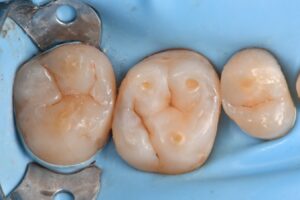

October 13, 2025 Direct Restoration #ClamplessDME #GarrisonCompositight #MajestyES2Universal Previous Post Next Post